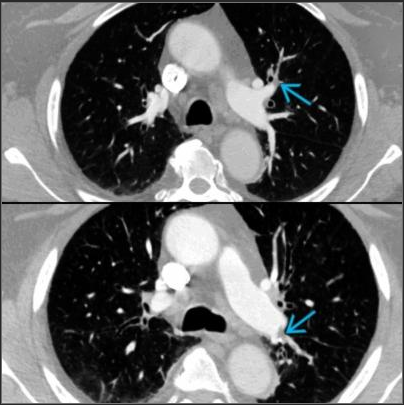

VQ Scan

Principles, Indication, and Examples

Evaluation of PE

- Ventilation: Xenon gas / DTPA

- Perfusion: 9mTc labelled microspheres or MAA

- Look for mismatched defects